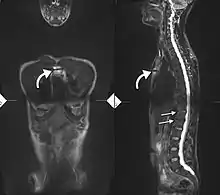

34-year-old male with AS. Inflammatory lesions of the anterior chest wall are shown (curved arrows). Inflammatory changes are seen in the lower thoracic spine and L1 (arrows).

If these criteria still do not give a compelling diagnosis magnetic resonance imaging (MRI) may be useful.[21][23] MRI can show inflammation of the sacroiliac joint.